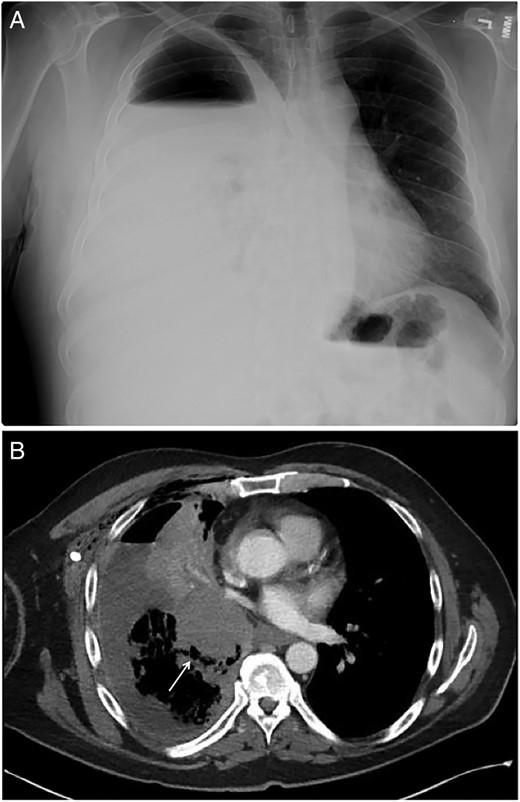

A 57-year-old male with a past medical history of stage IIB (T3b, N0) melanoma of the right superior neck and heavy marijuana use presented to the emergency department in April 2015 with progressively worsening dyspnea, right-sided pleuritic pain and hemoptysis. The patient was afebrile and normotensive. Physical examination was unremarkable except for decreased breath sounds at the right lung base. Laboratory values were within normal range and showed no leukocytosis. A subsequent chest X-ray showed right-sided hydropneumothorax with mild right-to-left mediastinal shift (Fig. 1A). A chest computed tomography (CT) scan confirmed the presence of a right infrahilar mass (Fig. 1B). The patient was admitted to the medicine service for management of hydropneumothorax.

(A) Anterior–posterior chest X-ray showing large right-sided hydropneumothorax with mild right-to-left mediastinal shift. (B) Chest CT showing a right infrahilar mass (arrow) occluding bronchus intermedius with post-obstructive airspace disease within the right lower lobe.